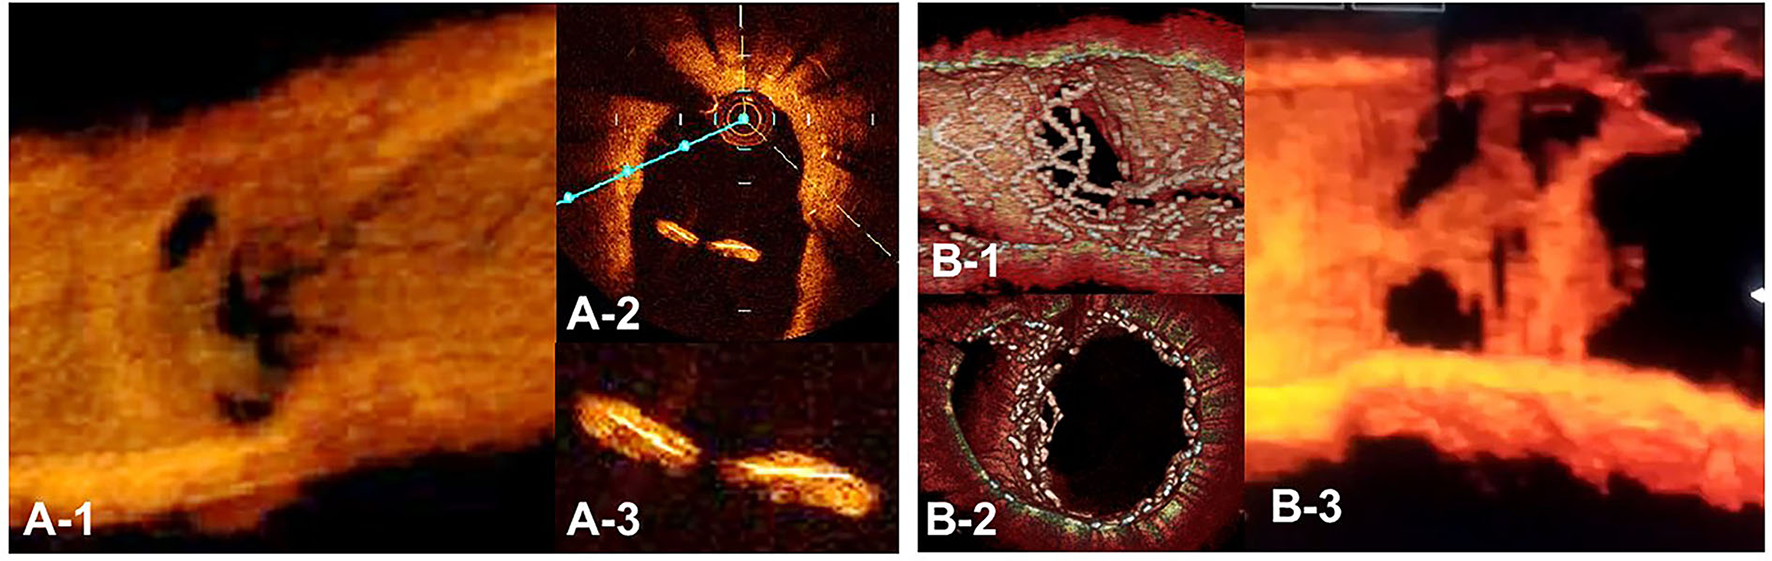

Figure 12

Optical coherence tomography (OCT) image of intimal proliferation on jailing struts at long-term follow-up period. A. One-year follow-up after crossover stenting with a synergy stent in the left anterior descending artery (LAD) without the fenestration of the diagonal branch. (A-1) 3D vessel view shows complete intimal coverage on the stent struts even in the jailing struts on the diagonal branch ostium with some luminal narrowing. (A-2) 2D imaging on the bifurcated site. (A-3) magnified view of the jailing struts. Complete intimal coverage of all surfaces of the struts was completed. (B) 3D OCT image after culotte stenting in LAD and diagonal branch using resolute integrity stents with significant metallic carina formation remaining (B-1: immediately after stenting, perpendicular view, (B-2) view from proximal to the bifurcation). (B-3) Two-year follow-up. 3D OCT image shows intimal coverage along the struts of the metallic carina, with several holes remaining (Supplementary Movie 13).

3D OCT imaging demonstrated that angio-guidance results in a lower success rate of optimal guidewire recrossing and a greater impact of link connection on the removal of jailing struts from the SB ostium than expected (4, 6). Ideal distal cell wiring in the LF type, which leads to optimal SB dilation with less ISA, was achieved in only 51% (54/105) of cases, even with 2D or 3D OCT guidance (4). In OPTIMUM, a randomized trial comparing 3D OFDI guidance and angio-guidance in coronary bifurcation stenting, angio-guidance produced more ISA than did 3D OFDI guidance (27.5 ± 14.2% vs. 19.5 ± 15.8%, P = 0.008) (6). Less optimal results in angio-guidance than expected may be one of the mechanisms for the failure of a conceptually perfect procedure. Discordance in the severity of SB stenosis after MV stenting between quantitative coronary angiography and physiological assessment of fractional flow reserve (FFR) is well-known, and FFR-guided SB treatment has been proposed to avoid unnecessary treatment in the SB with a high FFR value (36–38) (Figure 11A). However, computer simulation or bench testing of coronary flow in the strut-jailing or narrowed SB indicates turbulent flow behind the strut with low shear stress at the SB ostium (26, 39, 40), which might lead to stent thrombosis, restenosis, or fatal events (39, 41, 42). An ideal SB opening without SB stenosis or shifted carina indicates the restoration of optimal coronary flow circumstances in the bifurcation (Figure 11B, optimal treatment). Although the final KBI is expected to solve this issue, acceptable efficacy has not been found in several randomized trials and meta-analyses (19, 20). Angio-guided guidewire recrossing only was available in these clinical studies, in which more than half of the cases might be of suboptimal wiring or undesirable jailing strut configurations (LC type) for SB dilation (Figure 11B, suboptimal treatment). A long-term follow-up OCT study demonstrated more thrombus attachment and intimal proliferation on the jailing struts and narrowing of the SB ostium (40, 43–45) (Figure 12, Supplementary Movie 13). Elevation of the accuracy of guidewire recrossing to >90% under 3D OCT guidance and subsequent optimal SB dilation have great potential to improve the clinical outcome of provisional stenting. In 2-stenting, accurate guidewire recrossing to the optimal distal cell requires one time for the SB in systematic T-stenting and TAP, and two times for both MV and SB in culotte stenting. Therefore, the low performance of angiography-guided guidewire recrossing might weaken the clinical outcome of these stentings; in particular, the success rate of ideal optimal guidewire recrossing in both MV and SB (50–66% in each branch) is estimated to be <50% in culotte stenting, which might be one reason that its significant advantage over other 2-stentings has not been reported (46–48) except for TAP stenting (49) regardless of excellent performance in bench testing (27). The risk of restriction of MV stent expansion (Figure 5) is listed as a significant disadvantage compared to DK-crush stenting (29, 46, 50) with a higher probability of suboptimal guidewire recrossing or undesirable jailing strut pattern (LC type). Since some metallic carina formation is allowed in crush stenting, strict guidewire recrossing to the SB is not required except for abluminal wiring outside of the SB stent. Although guidewire recrossing before final KBI is easier than crush stenting, wiring to outside of the hole created by first KBI should not be done to avoid further deformation of the jailing struts in DK-crush stent. Therefore, accurate assessment of guidewire recrossing in the optimal cell and monitoring of the stent configuration during the procedure under 3D OCT imaging guidance is more essential in complex 2-stenting.